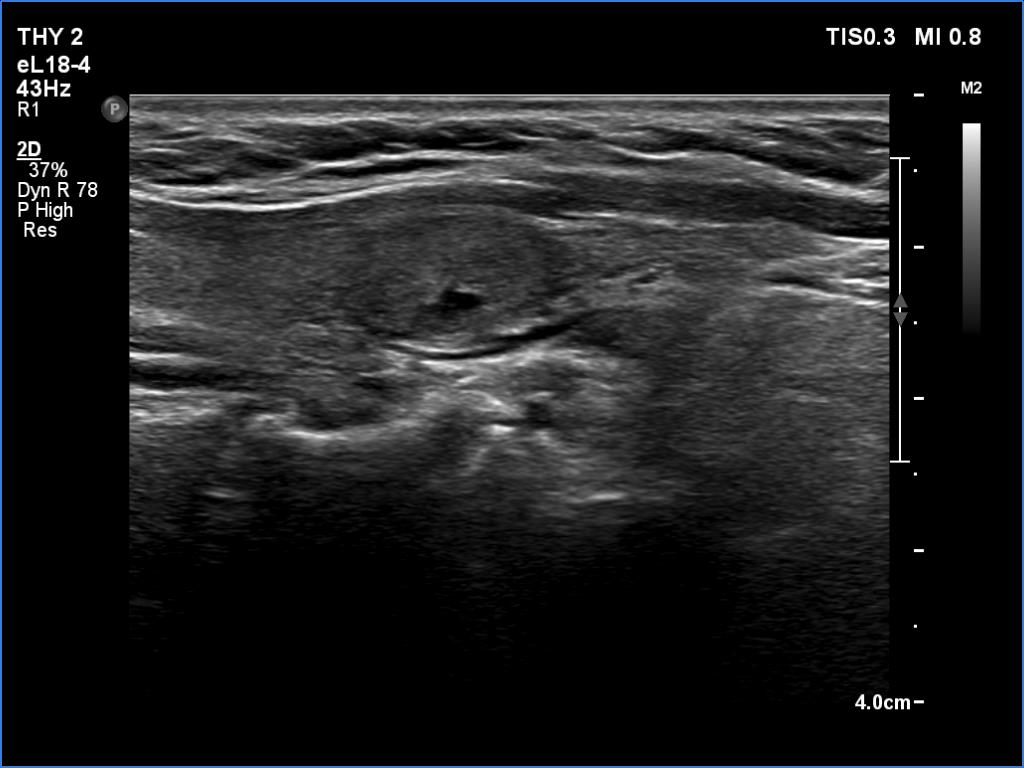

Initial examination (first row of images):

Clinical presentation: A 47-year-old woman was referred for evaluation of complaints suggesting subacute thyroiditis. She has had neck complaints and subfebrility for a month. First, the right lobe became painful, two weeks later the pain migrated to the left lobe. Non-steroid anti-inflammatory drug and 20 mg methimazole were administered by the GP. The complaints ceased 10 days before the present examination. A week after the beginning of the complaints, the CRP was 107 mg/L, the FT4 39.1 pM/L.

Palpation: Both lobes were firm, the left lobe was a bit tender on palpation.

Laboratory examination: TSH 0.01 mIU/L, FT4 17.9 pM/L, CRP 3.0 mg/L.

Ultrasonography: Both lobes were moderately hypoechoic and had a cloudy appearance. Both lobes had discrete lesions without oncological importance. The vascularity was decreased.

Diagnosis: subacute, granulomatous de Quervain's thyroiditis.

Suggestion. Ceasing the thyrostatic therapy and the anti-inflammatory drug. Repeat examination in three months, if the complaints would recur, at once.